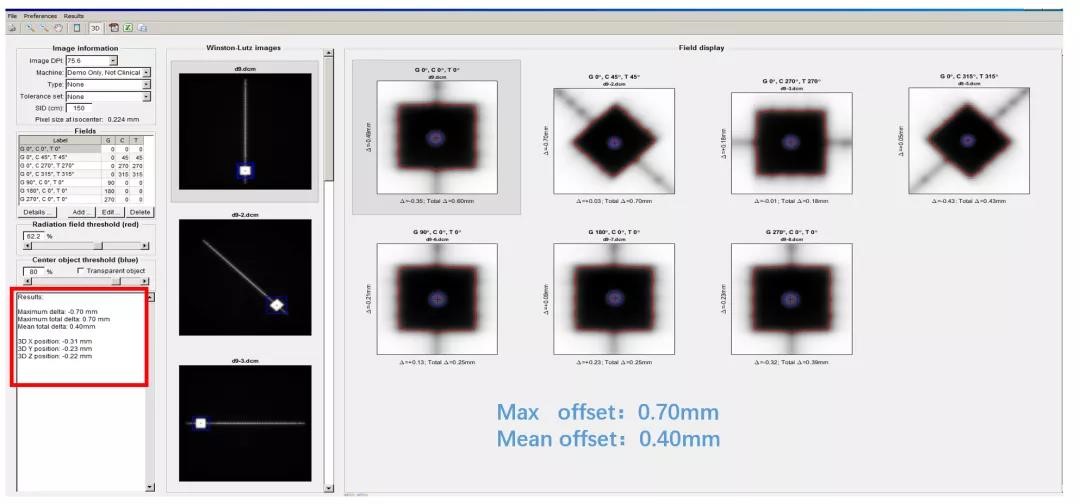

1、Winston-Lutz-Gao Test

一个等中心多靶点照射,难免会出现某些靶点距离等中心较远的情况,这时候我们怎么确保治疗的精度?其中一项很有意义的测试就是设计偏中心照射野进行Winston-Lutz测试。

在偏中心9cm处,开一个2*2cm的小野,

进行Winston-Lutz测试

使用DoseLab分析结果显示,最大误差为0.7mm,

治疗精度完全可以控制在1mm以内